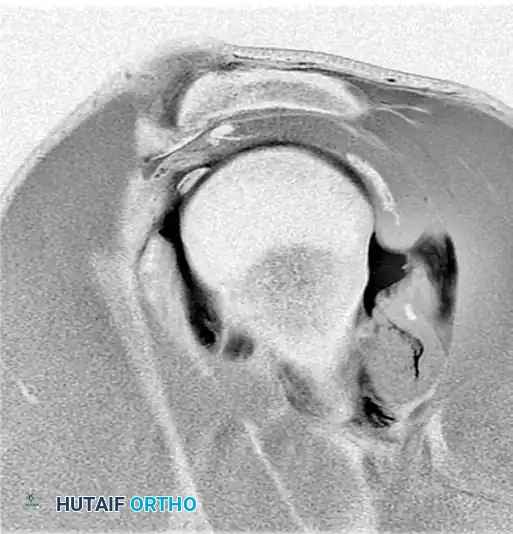

Preoperative magnetic resonance imaging (MRI) or MR arthrography is essential for identifying specific capsuloligamentous injuries. One such critical finding is the Humeral Avulsion of the Glenohumeral Ligament (HAGL) lesion, which can be easily missed if not specifically sought.

Figure 47-32 (A, B, C): MR angiograms demonstrating a HAGL lesion. Note the characteristic J-sign indicating the avulsion of the inferior glenohumeral ligament from its humeral attachment.